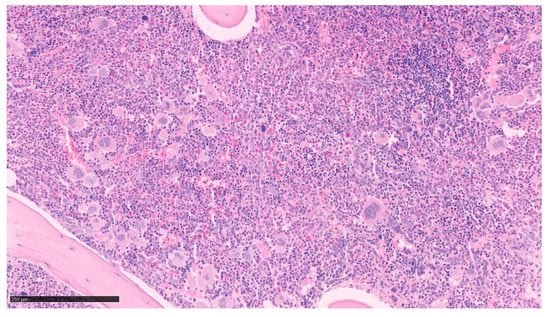

2.3. Primitive Myelofibrosis (PMF)

| Myelogram/ BM biopsy | Megakaryocytic proliferation with atypia and large spectrum of shapes (abnormal maturation, hyperchromatic, hypo or hyperlobulated, irregular nuclei (bulbous, “cloudlike”), tight clusters Reticulin fibrosis ≤ grade 1 (pre-PMF) Reticulin and/or collagen fibrosis grade 2 or 3 (overt PMF) [15] | |